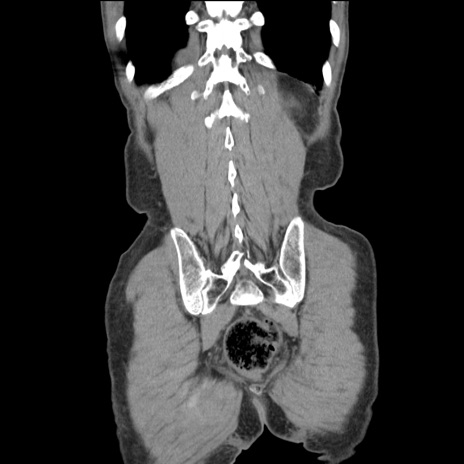

横断像